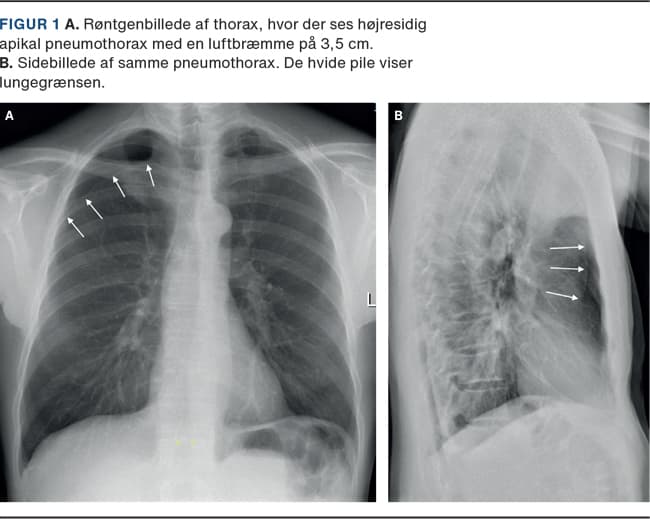

En lungerask patient med kroniske nakke-ryg-smerter søgte en alment praktiserende læge pga. en subjektiv fornemmelse af »tung vejrtrækning«. Han blev henvist til røntgenoptagelse af thorax, hvor man fandt højresidig pneumothorax (Figur 1).